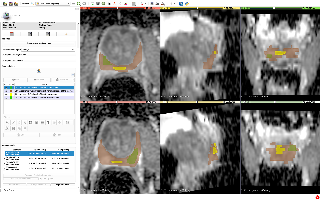

MMWHS

| MMWHS | 心脏 | 分割 | CT / MRI | 20CT、20MRI | 类别 | nii |

mmwhs是心脏分割数据集,共有8类,MRI和CT两种模态 相关项目: Hybrid Loss Guided Convolutional Networks for Whole Heart Parsing